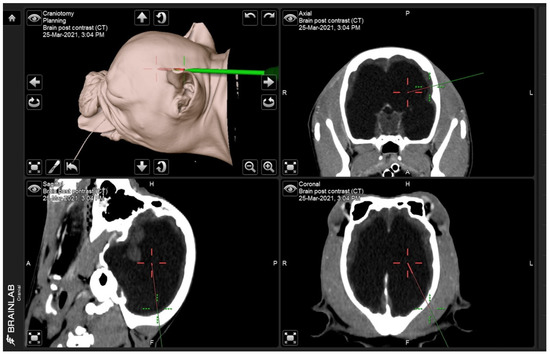

2.1. Treatment